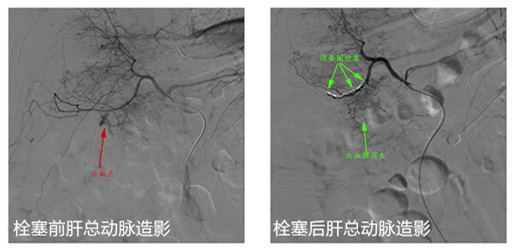

急诊介入团队即刻启动。经过充分的术前准备,祁家祥带领介入团队在介入导管室为患者实施了介入栓塞术。术中造影证实,患者胃十二指肠动脉分支为出血血管,并予以弹簧圈栓塞,栓塞后出血血管不再显影,患者血压逐渐恢复正常,术后病人生命体征平稳。